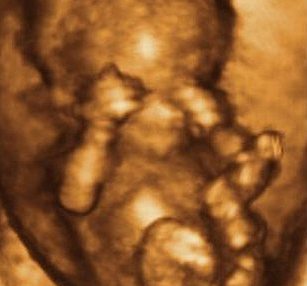

Grupy Wsparcia [WSPARCIE]

Program dla rodziców,

którzy

dowiadują się, że urodzi im się dziecko z wadą, lub że istnieje duże

ryzyko okołoporodowe. Nowoczesna diagnostyka prenatalna umożliwia także

i to - udzielenie rodzicom wsparcia emocjonalnego jeszcze przed

urodzeniem chorego dziecka.

fot: Mariusz